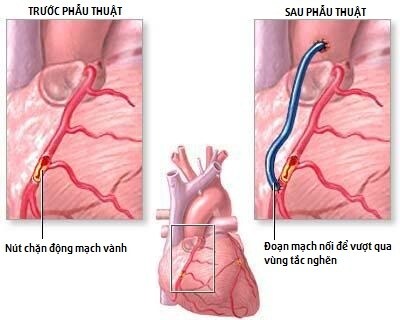

Phẫu thuật bắc cầu mạch vành: Giải pháp giảm nhồi máu cơ tim

Phẫu thuật bắc cầu động mạch vành không chữa khỏi bệnh tim gây ra tắc nghẽn, chẳng hạn như xơ vữa động mạch hoặc bệnh mạch vành. Tuy nhiên, nó có thể làm dịu các triệu chứng, chẳng hạn như đau ngực và khó thở.